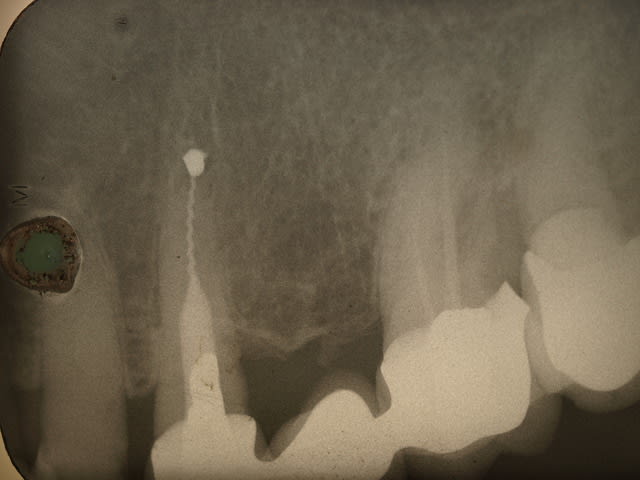

Euh .......les gas y a pas un truc qui vous gêne là ? Vous avez vu les radios ?

Premièrement il faudra que m'expliquer comment le bridge qui au départ est infiltré voir carié sur la 4 se retrouve comme par magie ré-adapté.

Le tenon n'est pas le même

Le traitement endo n'est pas le même

La 7 est couronnée (cantilever) sur une radio , pas sur la radio pré-op

Le niveau osseux n'est pas le meme sur les 2 radios

BREF IL NE S'AGIT PAS DU MEME PATIENT....

Tu dis avoir démonté le bridge et reposé tel quel , ce qui est faux au vu de la radio pré-op en page 5..... le tenon , ete le trt endo sont différents .

Tu as donc inventé une technique pour réadapter des prothèses non adaptées ....... le hyatus a disparu comme par magie , donc 2 possibilités :

- Tu as refait le bridge et tu ne le dis pas

- La radio pré-op est de quelqu'un d'autre

Les autres radios je m'en fous , je dis juste qu'entre les deux radios (15 ans) il y a du y avoir une intervention divine ....

Je te trouve bien hargneux sur ce bridge, parce que si tu regardes bien les radios tu vois bien que c'est le même patient quand-même, et que la 7 a été couronnées par la suite. Les radios ont une incidence un peu différente.

Si 15 ans sépare la radio pré opératoire de la dernière radio, force et de constater que la réimplantation a fonctionné.

Je note néanmoins une cratérisation apparue autour de la partie cervicale de la racine réimplanté, suite à l'intervention, mais stabilisée par la suite.